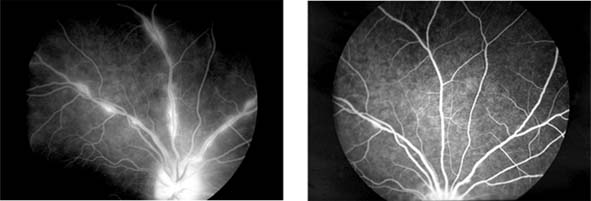

Central Retinal Vein Occlusion (new window  Figure 15-7)

Figure 15-7

Figure 15-7: Central retinal vein occlusion. Left: Photograph shows linear hemorrhages in the nerve fiber layer and punctate hemorrhages in the deeper retinal layers. Right: Fluorescein angiogram shows dilation of the veins.

Fundus examination shows dilated tortuous veins with retinal and macular edema, hemorrhages all over the posterior pole, and cotton-wool spots. The arterioles are usually attenuated, indicating generalized microvascular disease.

The prognosis for vision is poor. Fluorescein angiography demonstrates two types of response: a nonischemic type, with dilation of retinal vessels and edema; and an ischemic type, with large areas of capillary nonperfusion or evidence of retinal or anterior segment neovascularization. In 93% of ischemic and 50% of nonischemic central retinal vein occlusions, the ultimate visual acuity is less than 20/200.

Retinal Branch Vein Occlusion (new window  Figure 15-8)

Occlusion of a branch vein should be viewed as part of the spectrum of central retinal vein occlusion. Investigations are similar in the two conditions, but arterial disease-particularly hypertension-is common. Branch retinal vein occlusion occurs more frequently in the superotemporal and inferotemporal regions and particularly at sites where arteries cross over veins, and only rarely where veins cross over arteries.

Figure 15-8

Figure 15-8: Retinal branch vein occlusion. The affected segment of retina shows changes of reduced perfusion. This results in irregularity of the arterioles and veins, areas of capillary closure, and dilated capillaries with microaneurysms.